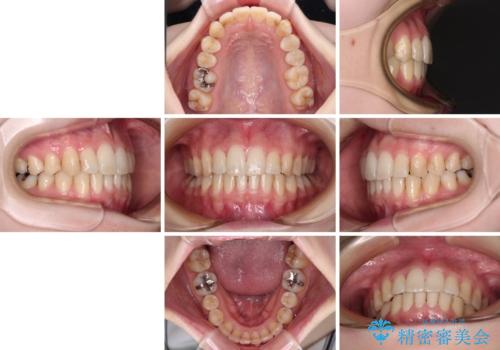

矯正治療後には、目立つ銀歯と隣接するむし歯をセラミックインレーにて修復治療することとしました。

左右ともに奥歯の咬み合わせには大きな問題がなく、窮屈な歯列を解決すれば歯列を整えることできたため、僅か1年で終えることができました。